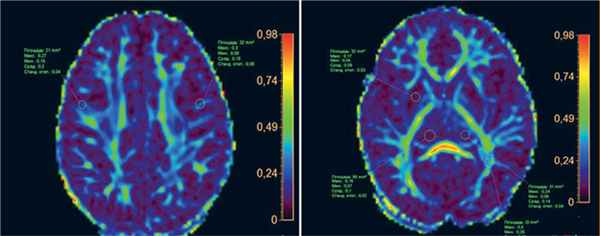

Пример изменений на МРТ у детей с вирусными энцефалитами, выявляемых с помощью фракционной анизотропии, представлен на рис. 2.

Рис. 2. МРТ головного мозга пациентки Х., 4 года: энцефалит цитомегаловирусной этиологии, острый период заболевания

Примечание. Снижение значений фракционной анизотропии при выполнении диффузионно-тензорной методики (DTI) в очагах косвенно свидетельствует о наличии в них цитотоксического отека; отмечается также сохранение целостности трактов (собственные данные).

При герпетическом энцефалите с помощью мультивариантного анализа было установлено, что ограничение диффузии на МРТ достоверно коррелирует с неблагоприятным исходом заболевания, в то время как расположение или распространенность очагов при FLAIR-/T2-исследовании не выявили достоверной связи [31, 32]. У новорожденных применение DWI при герпетическом энцефалите позволяет выявлять поражение головного мозга на ранних этапах развития заболевания: наличие билатеральных очагов в белом веществе мозга достоверно коррелирует с неблагоприятным прогнозом исхода [33]. Также при вирусном энцефалите у детей показано, что параметры артериальной спин-меченой перфузии (arterial spin-labeling perfusion) коррелируют с неблагоприятным исходом по смертности и развитию судорожного статуса [34]. Методика МР-спектроскопии может быть эффективной в выявлении маркеров разрушения клеточной стенки и часто применяется для этих целей (рис. 3).

Пример изменений, не выявленных методом структурной МРТ, но обнаруженных с помощью мультипараметрической МРТ у ребенка с вирусным энцефалитом, представлен на рис. 4.

Рис. 4. МРТ головного мозга пациента М., 10 лет: энцефалит цитомегаловирусной этиологии

Примечание. А, Б — убедительные изменения на Т2-, FLAIR- и DWI-режимах отсутствуют. В, Г — снижение фракционной анизотропии в правой ножке (1) и полушарии мозжечка (2, 3) в сравнении с контралатеральной стороной (косвенные признаки снижения нейрональной плотности), сохранение целостности трактов (собственные данные).